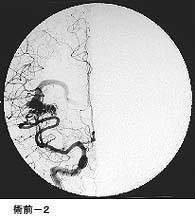

破裂脳動脈瘤に対するコイル塞栓術GODコイルだとちょっと古いので、コイル塞栓術とする方が良いのではないかと思います。

術後 コイルにより動脈瘤が写らなくなりました。